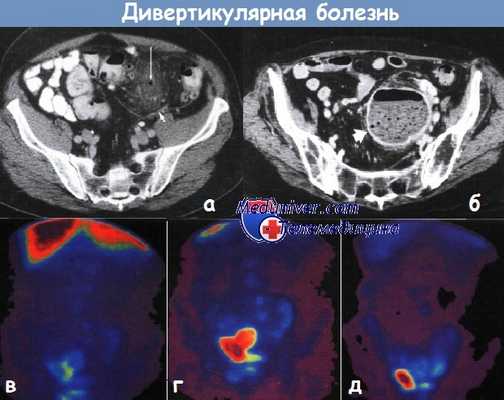

а - Маленький околотолстокишечный абсцесс при дивертикулите. Фокус скопления воздуха наблюдается вне контура просвета кишки (показано длинной стрелкой) в центре мягкотканного тяжа жировой ткани, идущего к сигмовидной кишке.

В брыжейке сигмовидной кишки видна жидкость (короткая стрелка). Компьютерная томография.

б - Большой околотолстокишечный абсцесс при дивертикулите. Полость абсцесса содержит воздух и остатки тканей (показано стрелкой), толстая стенка абсцесса усиливает контрастность.

Компьютерная томография.

в,г,д - Радиоизотопное исследование с применением 99mТс у пациента с клиническими признаками сепсиса при отсутствии первичного очага. Через 1 ч (в) обнаружено нормальное рас пределение изотопа в печени и селезенке. Через 3 ч (г) изотоп наблюдают в кишке, и он накапливается в полости таза.

Через 22 ч — остатки изотопа наблюдают только в тазовом абсцессе (д).